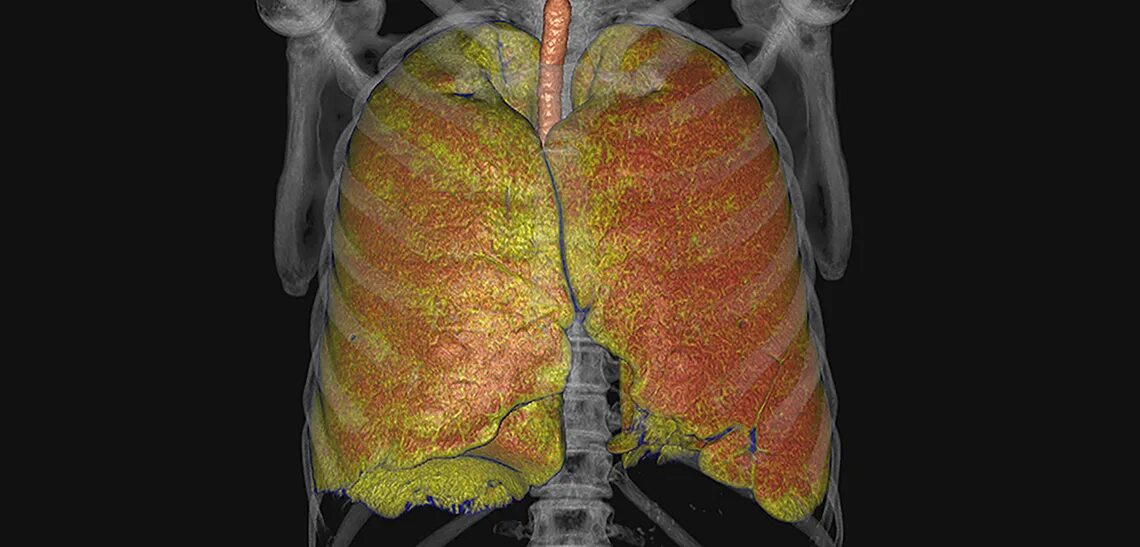

Снимок курильщика